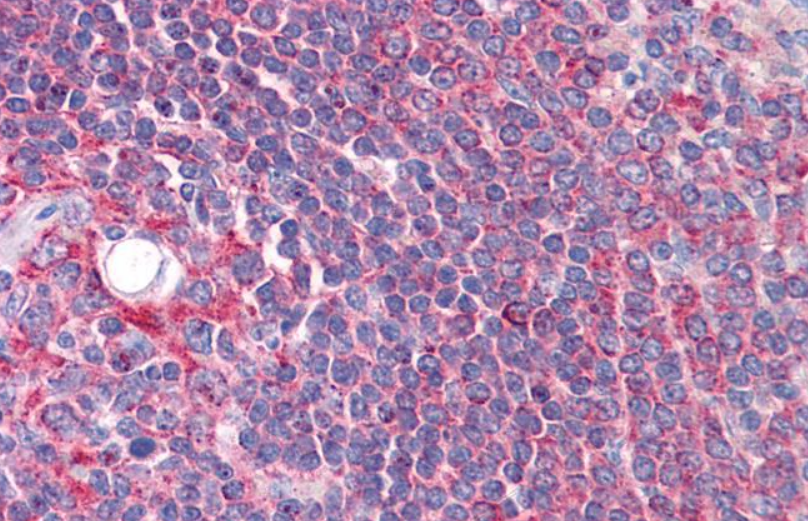

10 μg, 100 μgChemerin Rabbit Polyclonal Antibody [orb156351]

IF, IHC-Fr, IHC-P

Bovine, Porcine

Human, Mouse, Rabbit, Rat

Rabbit

Polyclonal

Unconjugated

100 μl, 200 μl, 50 μlGoat anti-CYP26B1 Antibody [orb19329]